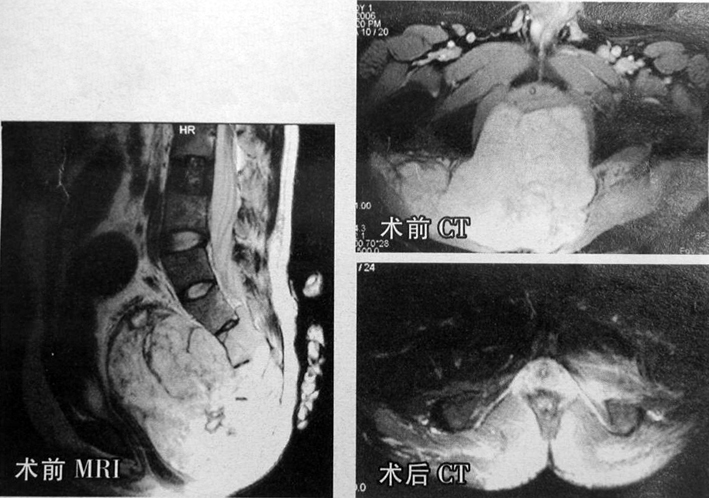

北京大学第三医院骨科刘忠军教授为1例骶部巨大脊索瘤患者成功施行了手术治疗,并保留了患者部分骶神经。患者为29岁男性,因腰腿及左侧臀部疼痛就诊,入院时已无法取坐位,并伴有大、小便失禁。检查后确诊患者罹患骶部脊索瘤,肿瘤占据大部分盆腔,已包埋了患者骶骨及骶部的血管、神经,并已压迫周围脏器。手术采用前路松解粘连组织,加后路切除肿瘤并行内固定方案,术者精细准确剥离被肿瘤组织包裹的骶神经,以保留部分骶神经功能。历时14个小时后,重达1.9 Kg的脊索瘤被完整剥离并成功切除。术后恢复顺利。